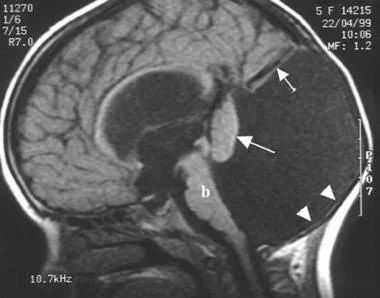

МРТ

МРТ является методом выбора при диагностике мальформации Денди-Уокера.

Гипоплазия червя с его низким расположением.

Кистозное расширение четвёртого желудочка, выдающаяся в заднюю черепную ямку. При данном состоянии доли мозжечка подвержены антеро-латеральному смещению.

Увеличенная в размерах задняя черепная ямка

У 75-90% пациентов выявляется обструктивная гидроцефалия с наиболее частой причиной — стеноз на уровне водопровода.